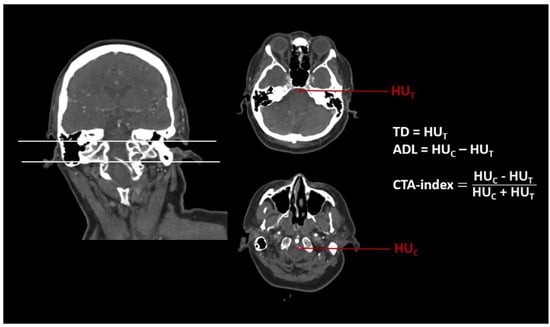

Within the perviousness cohort, thrombus perviousness parameters were already assessed (see [16]). Mean density values of the CTA in ROIs (a) within the occlusion site (labeled as (T), measuring points were placed about 1.5 mm distal of the visible stop of contrast agent in consideration of appositional thrombus growth) and (b), at a reference point (labeled as (C), within a preceding vessel section that is regularly filled with contrast agent at a distance to the occlusion site), were used for further analyses. Imaging markers such as pure thrombus density in CTA (TD = HUT), absolute density loss (ADL = HUC − HUT), and relative thrombus attenuation (CTA-index = (HUC − HUT)/(HUT + HUC), modified according to [21]), were calculated for each patient (Figure 2).

From preceding perviousness measures, density values of CTA image ROIs within the thrombus and the reference point of the perfused vessel were extracted (Figure 2). ADL and CTA-index were assumed to measure perviousness. Lower values indicated a higher perviousness.

Figure 2. Example of an assessment of CT imaging markers pure thrombus density (TD), absolute density loss (ADL), and CTA-index (relative thrombus attenuation) for a patient (male, 60 years) with an acute basilar artery occlusion. ROIs for measurements of mean Hounsfield Units (HU) were placed at the occlusion site (T) and a reference point (C).